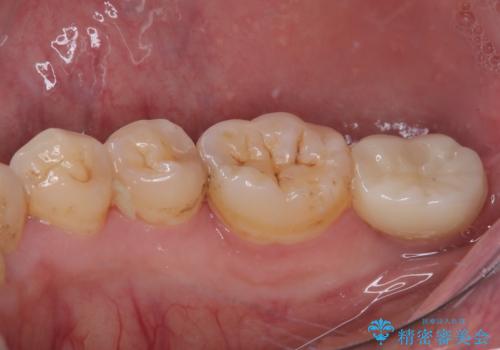

- 左下欠損部のインプラント治療を希望して来院された患者様です。

左下の欠損部を長期間欠損を放置していたことで、咬み合う上の奥歯が動いてしまっていたので、まずは上顎奥歯の部分矯正を行うこととしました。

理想的な咬み合わせに改善した上で、インプラント補綴治療を行うこととしました。